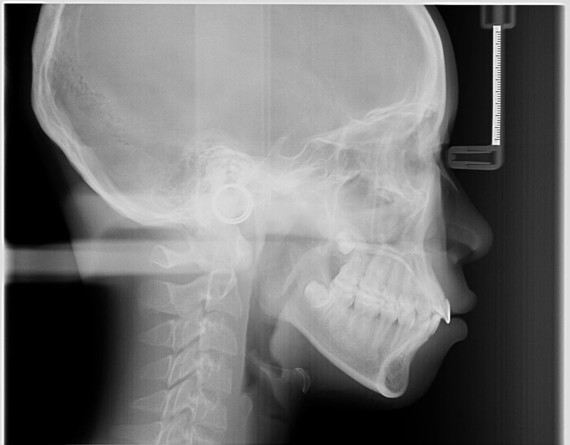

下颌骨侧位x片

图片尺寸828x934

之前拍的牙片

图片尺寸1080x682